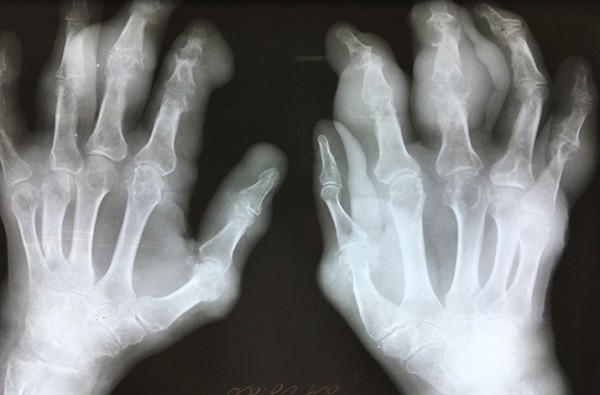

Те же тофусы при рентгенологическом исследовании — подагрическая деструкция костей кистей.